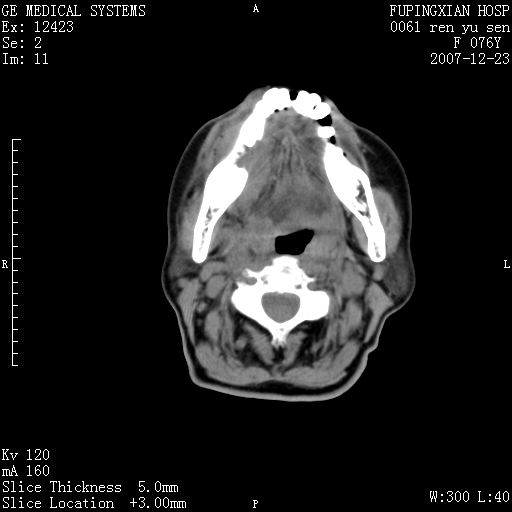

男性 76岁 下颌右侧磨牙区肿物数月, 约2.0*1.5cm大小波及颊舌侧,伴颌下淋巴结肿大。余(-)

右颈部颌下腺前可见一类圆形软组织密度影,密度不均,内见小片坏死区.颌下颈前可见两枚肿大淋巴结影.考虑淋巴结感染可能性大,建议增强扫描..

右侧第四磨牙缺失,局部牙槽骨质破坏,边界欠清晰,同侧颌下及竟不见多发肿大淋巴结显示。考虑肿瘤病变可能性大,感染待排